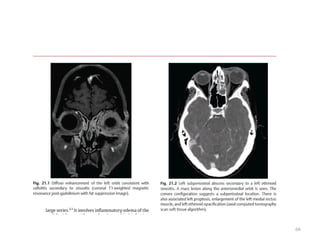

ORBITAL COMPLICATIONS

• Most commonly following ethmoid sinusitis

• Lamina papyracea

• Osteitis or as thrombophlebitic process of

ethmoidal veins.

65

• Superior orbital fissure syndrome- 6, 3,4 palsy

• Orbital apex – optic nervand maxillary division

of trigeminal